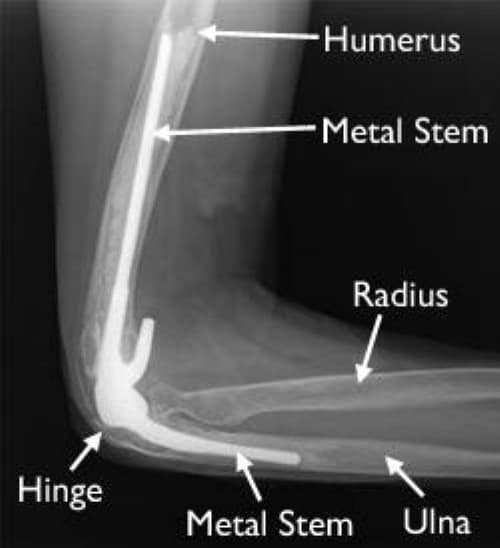

Мэс заслын явц

• 2 цаг орчим үргэлжилнэ

• Ерөнхий унтуулгатай мэс засалд орно

• Мэс заслын дараа эмнэлэгт дунджаар 5-6 хононо

Тохойн хиймэл үе солих мэс засал image2